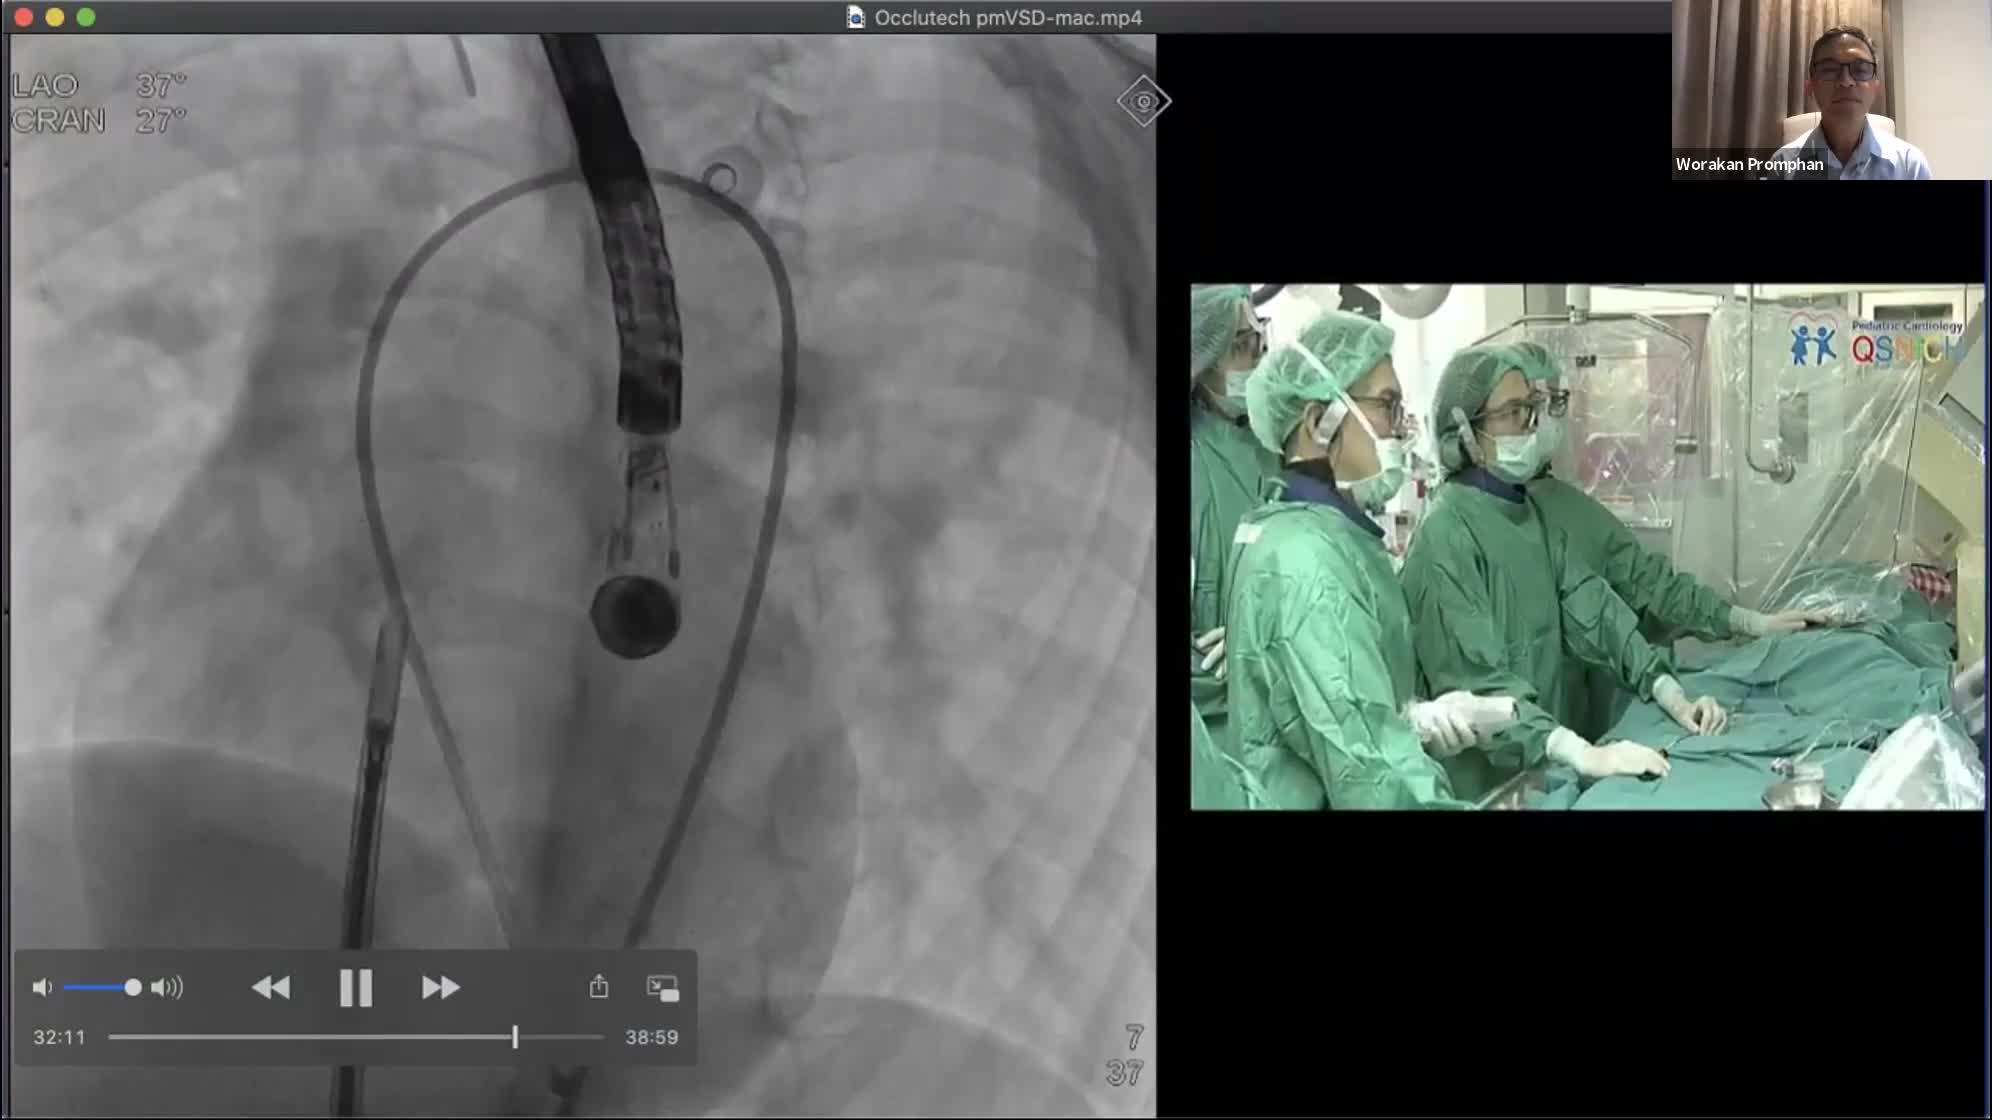

CSI CATHLAB LIVE - VSD CLOSURE WITH THE NEW OCCLUTECH PMVSD OCCLUDER (ANTEGRADE APPROACH)